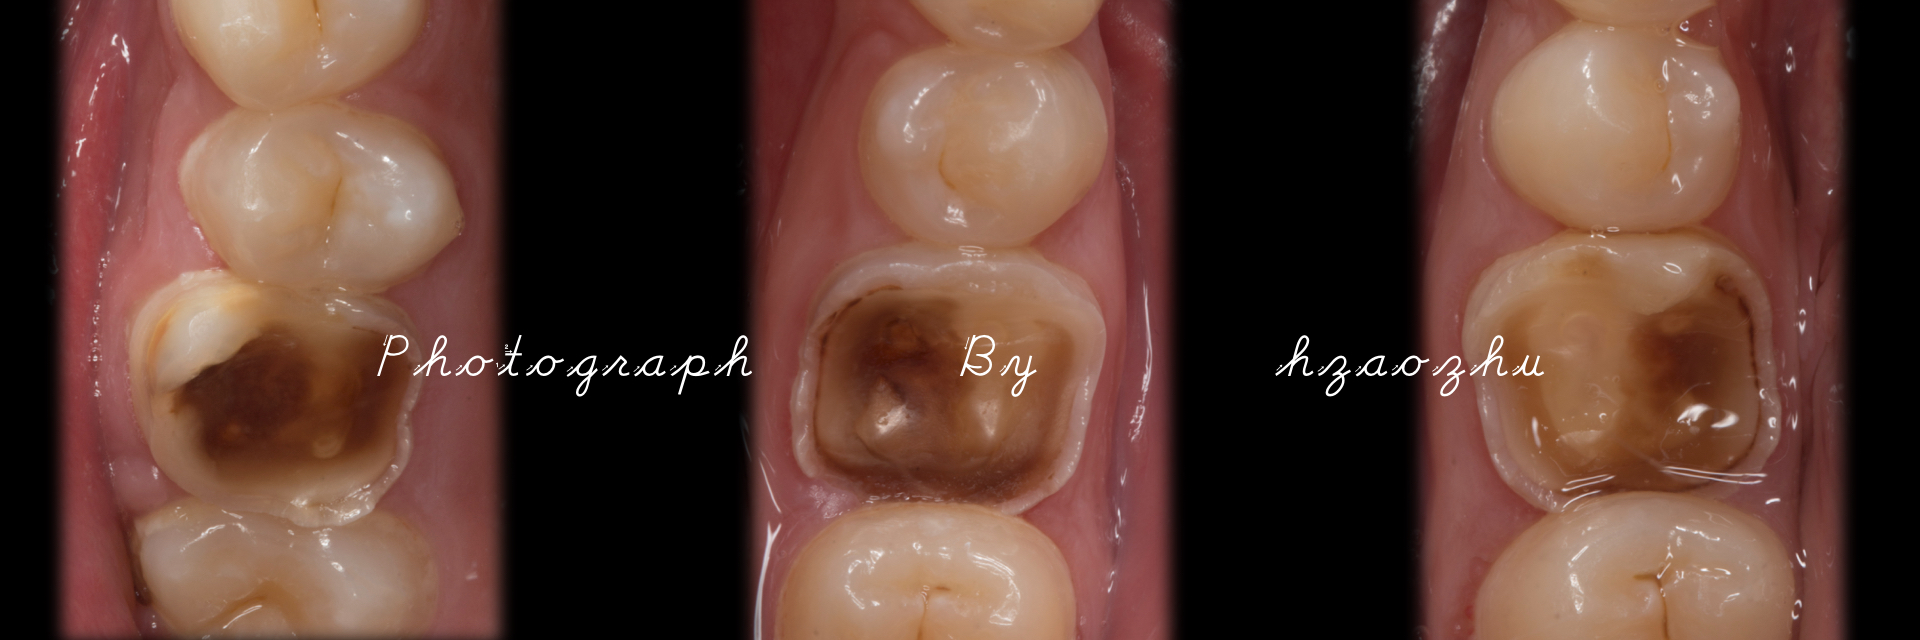

嵌体|E.Max .16.36.46

温州佳洁口腔 朱照鸿 医生 | 技师:尹群